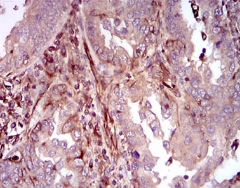

MAPK14 Mouse Monoclonal antibody[10B11]

IHC    1/200 - 1/1000